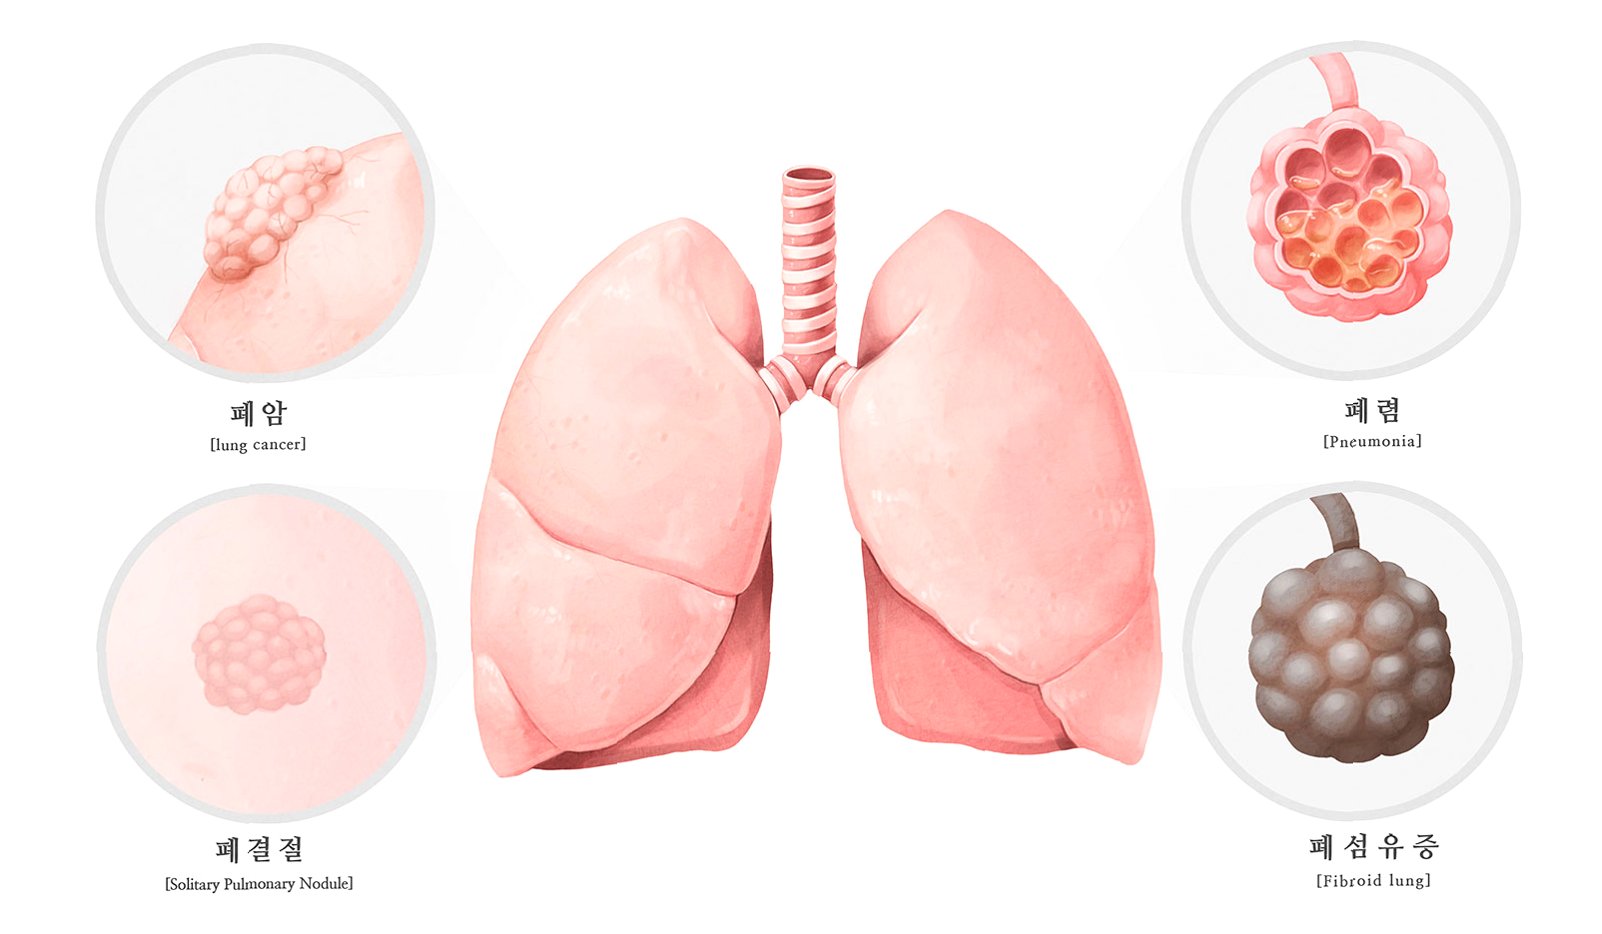

의료진은 처음에는 석회화된 부분만 제거하려 했으나, 손상 범위가 너무 넓어 폐 전체를 적출해야 한다는 결론에 이르렀습니다. 사이먼스 씨는 결국 왼쪽 폐를 떼어내는 수술을 받았습니다. 그는 “작은 먼지 한 톨이 내 인생을 이렇게 바꿀 줄 몰랐다”며 “수술 동의서에 서명하던 순간이 인생에서 가장 무거웠다”고 심경을 토로했습니다. 이처럼 외상으로 체내에 남은 이물질은 장기간에 걸쳐 석회화되며 염증이나 조직 괴사를 일으킬 수 있습니다. 특히 폐 조직은 통증 수용체가 적어 초기 증상 인지가 어렵고, 뒤늦게 발견되는 경우가 많아 주의가 필요합니다.

전문가들은 외상으로 인해 유리 조각이나 금속 파편 같은 이물질이 체내에 남을 경우, 장기간에 걸쳐 석회화가 진행되면서 염증이나 조직 괴사를 일으킬 수 있다고 경고합니다. 특히 폐 조직에는 통증 수용체가 거의 없어 초기에는 증상을 느끼기 어렵다가 뒤늦게 검진을 통해 발견되는 경우가 많습니다. 염증이 심해져 늑막이나 기관지를 자극하면 발열, 기침, 호흡곤란 등의 증상이 나타날 수 있으므로, 폐 건강에 대한 각별한 주의가 요구됩니다. 작은 이물질이라도 방치하면 심각한 결과를 초래할 수 있음을 사이먼스 씨의 사례는 명확히 보여줍니다.